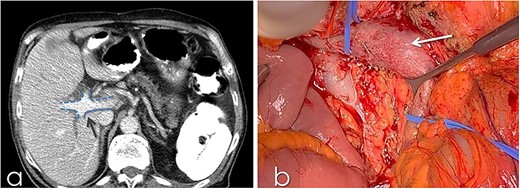

(a) Classification of IVC abnormalities; (b) variations of the branching of portal vein. MPV: main portal vein, RPV: right portal vein, LPV: left portal vein, RAPV: right anterior portal vein, RPPV; right posterior portal vein.

Duplication of IVC

The duplicated IVC appears with an incidence of 0.2–3%. [2, 8] A suggested classification is shown in Fig. 3 [9] Type 1 refers to normal IVC formation of the common iliac veins connection. Type 2a represents a duplicated IVC without communication between the two common iliac veins, whereas types 2b and 2c refer to duplicated IVC with interiliac communication from the left and right common iliac veins, respectively. Additionally, type 2d and 2e stand for duplicated IVC with interiliac communication from left and right internal iliac veins, respectively. In type 3, the left IVC formed by the merge of left and right common iliac veins. In type 4, there is no iliac connection and the infrarenal IVC is absent. In our case, the duplicated IVC is characterised as type 2a [9].

TRIFURCATION OF PV

Figure 3 presents the existing classification. [7, 13, 15] Type I shows the normal PV formation. In type II, the trifurcation of the PV is presented, whereas in type III, the right posterior PV (RPPV) represents the first branch of the MPV. Type IV and V refer to the separate origin of the branches of segments VII and VI correspondingly from the MPV. The last variant mentions the absence of PV bifurcation. In our case, a trifurcated PV, type II according to this classification, was noticed.